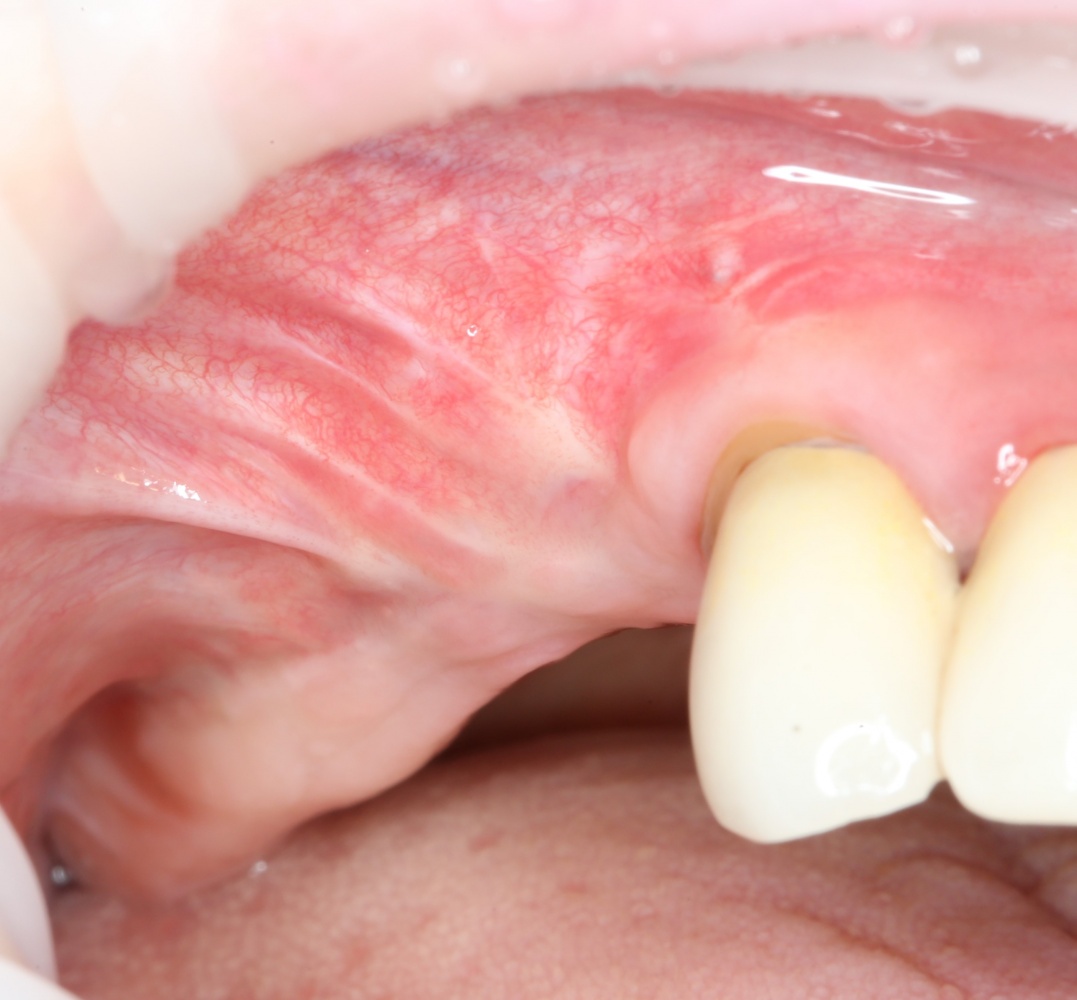

Выход простой: Делайте нижний край апертуры доступа как можно ниже. В идеале — почти впритык ко дну гайморовой пазухи. И вы удивитесь, насколько проще станет делать синуслифтинг при таком подходе:

Даже если вы делаете операцию над лункой удалённого зуба — здесь вам особенно важно сохранять контроль над дном, ибо длительно существующий периапикальный процесс нередко ведёт к образованию спаек, и риск перфорации очень высок. А иногда бывает и такое, что дно верхнечелюстной пазухи находится ниже апикальных частей лунки. В этом случае можно смело проводить нижнюю границу прямо по лункам — ничего страшного в этом нет, а хороший обзор в таких случаях гораздо важнее.